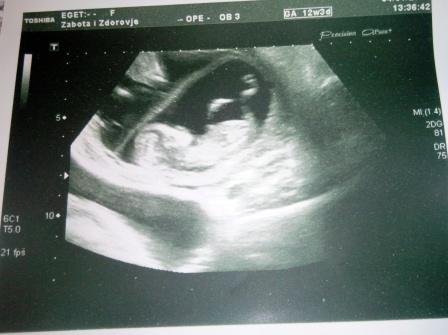

4.01. мы повторили узи,за 2 недели малыши подросли чуть ли не в 2 раза(с 37 и 38мм до 62 и 60мм).Развиваются согласно сроку,сердечки бьются в унисон 158 уд\мин. Проверили наличие хромосомных аномалий-оба малыша абсолютно здоровы,чему мы были несказанно счастливы.Теперь совместных фоток уже не получилось сделать,теперь каждый отдельно)))Матка расположена правильно,тонуса и угрозы нет,но мы все равно сбавили обороты нашей интимной жизни.

ну и фоточки моих любимых